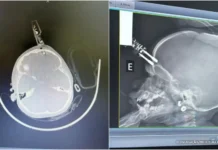

Bebê tem carregador de celular cravado na cabeça após queda em MG

MINAS — Um acidente doméstico assustou os moradores de Divinópolis, a 117 quilômetros de Belo Horizonte, na última segunda-feira (12). Uma menina de apenas...